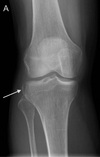

116

Chondrocalcinosis - in the knee this can be seen as linear calcifications of the meniscus and articular cartilage